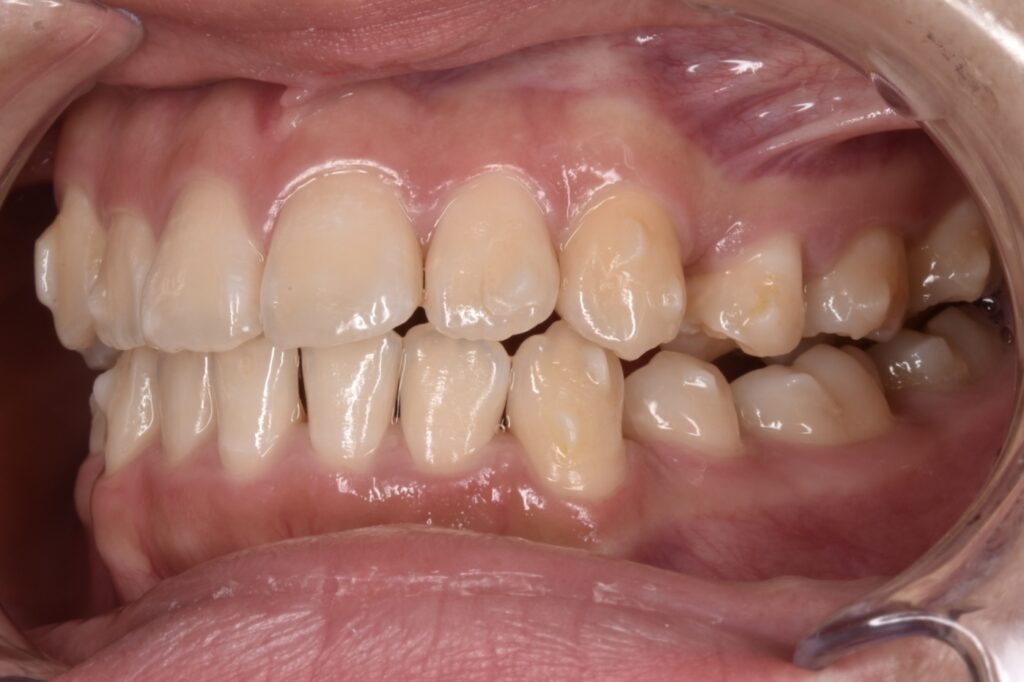

現状38枚目(矯正開始後10ヶ月)

現在矯正開始から38週経過し38枚目になっています。追加アライナーなし、順調に経過しています。八重歯感もだいぶ改善してきましたね。噛み合わせは本人様は全然気にならない様ですが最後に調整していきます。追加アライナーとゴムかけなどです。